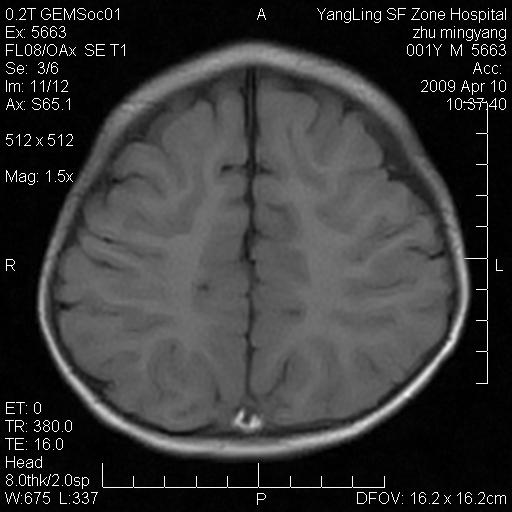

患者:1岁半,两天前外伤收住我院,ct检查小脑占位

考虑星形细胞瘤,建议增强

髓母细胞瘤或血管母细胞瘤,增强后可以鉴别;影像资料见 <。鱼博浪老师的《中枢神经系统ct与mr鉴别诊断》 小脑部肿瘤章节。

髓母细胞瘤或血管母细胞瘤!支持!

支持考虑髓母细胞瘤

考虑----髓母细胞瘤可能性大

考虑髓母细胞瘤或室管膜瘤。

支持髓母细胞瘤。

考虑髓母细胞瘤。

考虑髓母细胞瘤或星形细胞瘤

考虑髓母细胞瘤.

考虑髓母细胞瘤可能性大。

小脑肿瘤.考虑髓母细胞瘤可能.

就病灶部位及临床资料首先考虑髓母.